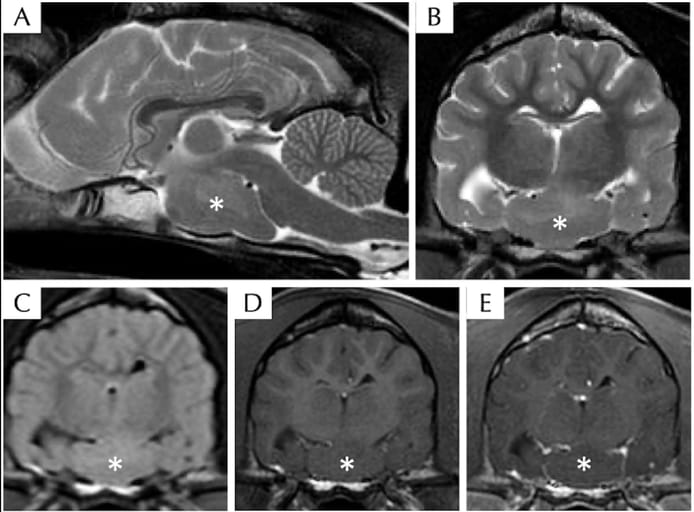

Magnetic resonance imaging of the head of a dog with suspected hypothalamic hamartoma, including T2W sagittal (A), T2W transverse (B), T2 FLAIR transverse (C), T1W pre- (D), and post- (E) contrast transverse sequences. There is a well-defined ovoid T2W, T1W, and FLAIR isointense compared to grey matter intra-axial mass (asterisk) without contrast enhancement at the level of the ventral middle cranial fossa extending along the cranial base within the region of hypothalamus.

MRI revealed a non-enhancing, ovoid suprasellar mass isointense to grey matter, consistent with HH. WGS identified 118 unique variants, including a high-impact splice acceptor variant in the SEPTIN8 gene, a deleterious missense mutation in UBXN10, and a start loss variant in BLOC1S1. These genes are associated with ciliogenesis and neurodevelopment. Treatment with fluoxetine and levetiracetam was ineffective. One year post-diagnosis, the dog remained clinically stable without medication, exhibiting persistent neurological signs.